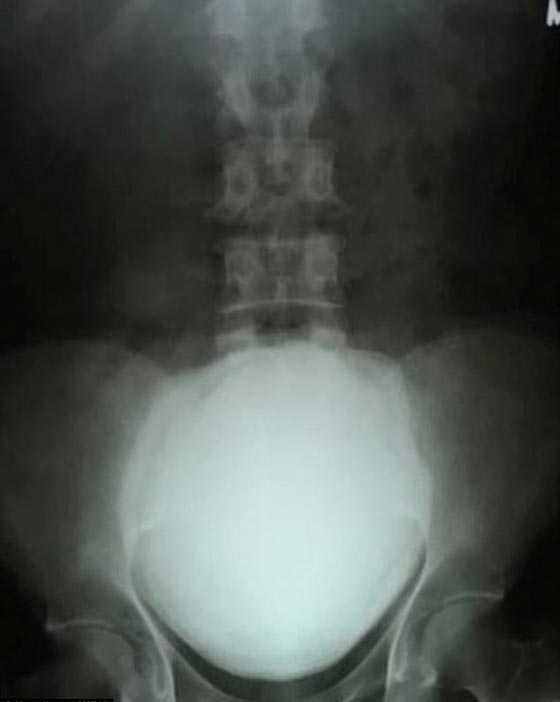

خضع رجل هندي لعملية جراحية لاستخراج حجر من الكالسيوم تكون داخل مثانته، وزنه 3 باوند ما يعادل نحو 1.36 كغم. وتوجه الهندي، ماهيش باتيل، البالغ من العمر 49 عاما، إلى المستشفى بعد معاناته من ألم مفاجئ في بطنه. وبعد الفحص عن طريق الأشعة السينية، اكتشف الأطباء حجرا يبلغ طوله 11.5 سم وعرضه 17 سم، داخل مثانة باتيل.

واستغرق الجراحون حوالي ساعة ونصف لإزالة الحجر من جسم المريض، وقد تم تصوير فيديو للعملية الجراحية في مستشفى سري سيناث في فلساد بالهند، يظهر من خلاله الأطباء وهم يكافحون من أجل استخراج الكتلة المتحجرة من دون التسبب في أية أضرار للمريض.

وأضاف أنه عادة ما يكون حجم الكتلة المتحجرة من الكالسيوم ما بين 1سم و3 سم، إلا أن الكتلة التي وجدت داخل جسم باتيل كبيرة بشكل مذهل، وبذلك يتفوق الحجر المستخرج حديثا على الرقم القياسي الهندي السابق، حيث استخرجت كتلة من جسم مريض بالسرطان العام 2010، وزنها نحو 2.6 باوند ما يعادل 1.18 كغم.